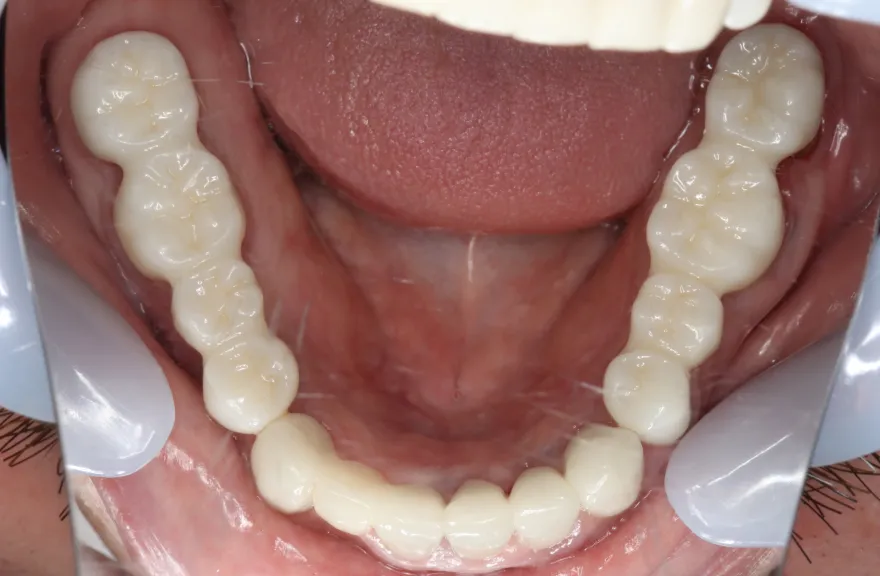

【治療例 2】金属を白くしたい63歳

写真の通りに治療を終了いたしました。

各所虫歯に侵食されていましたが、歯を残すことができたのでインプラントの数をおさえることができました。

下の前歯が先天的に1本欠損しており、そのため噛み合わせを構築することが難しいケースでした。矯正治療を併用することで前歯と奥歯をバランスよく噛ませることに成功しました。